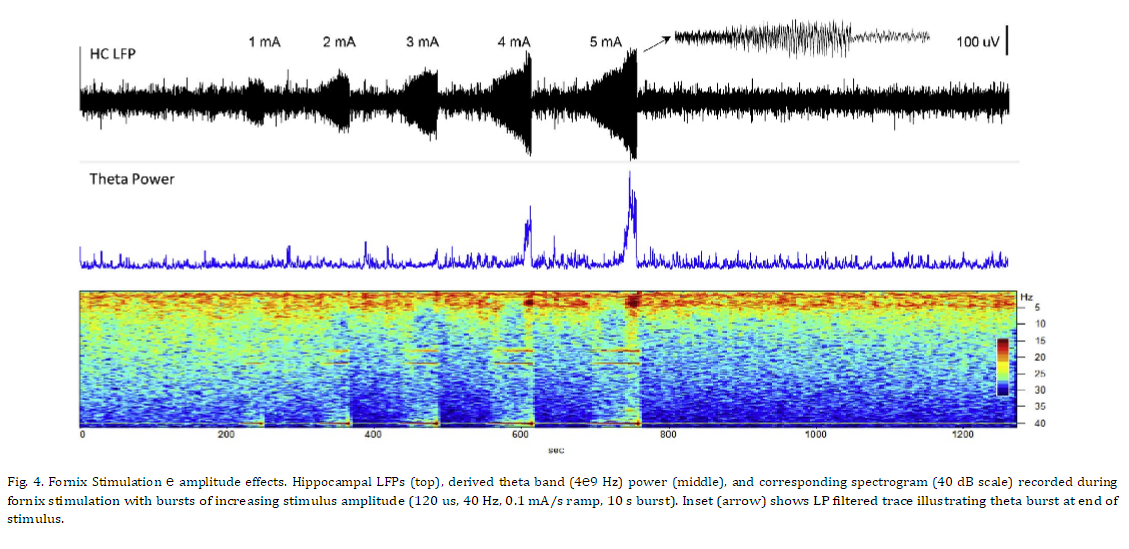

시상 자극에 대한 초기 연구와 직접적인 비교를 제공하기 위해 해마 LFP 활동에 대한 다양한 자극 진폭 및 빈도의 효과를 평가했습니다. 그림 4는 증가하는 진폭의 자극(40Hz)의 10초 램프 시작 버스트에 대한 해마에 기록된 반응을 보여줍니다. 더 낮은 자극 진폭에서 해마 활동의 억제가 있었고 자극 중에 발생한 세타 및 더 높은 주파수 대역에서 분명했지만 이월 효과는 거의 없었습니다. 자극 진폭이 증가함에 따라 이 억제 효과는 그림 4에 제시된 마지막 두 자극에서 볼 수 있는 세타 활동의 임계치 의존적 흥분 폭발로 전환되었습니다. 더 높은 주파수 대역(베타, 감마)이 감소된 낮은 주파수 성분(델타, 세타). 서로 다른 주파수의 Fornix DBS(그림 5)는 유사한 응답 패턴을 생성했으며 자극 진폭의 느린 증가 동안 20Hz 이상의 자극 주파수에서 LFP 억제가 분명했습니다. 이 예에서, 자극 수준이 프로그래밍된 최대값(4mA)에 도달함에 따라 더 높은 DBS 주파수로 생성된 세타 활동의 짧은 버스트(삽입)가 있었고, 이어서 낮은 주파수 LFP 활동이 상승했습니다. 이러한 자극으로 인한 세타 버스트는 오래 지속되는 효과를 가졌습니다. 그림 6에 보다 명확하게 설명된 것처럼 기본 해마 LFP 활동에 대해 설명합니다. 이 예에서 해마 활동의 12분 기간은 피험자가 조용히 쉬고 있는 상태에서 기록되었습니다. 5분의 기준선 기간 후, 해마 세타 버스트를 생성하기 위해 문턱 이상의 수준까지 뇌궁 자극이 천천히 증가했습니다. 자극 진폭이 증가함에 따라 짧은 억제 기간이 관찰된 후 상단 패널 스펙트로그램에서 볼 수 있는 짧은 세타 버스트가 관찰되었습니다. 이 세타 버스트와 자극 중단 후 해마의 LFP 활동은 기준선과 비교하여 현저하게 변화했으며 이러한 패턴은 자극 후 몇 분 동안 지속되었습니다. 전체 시험 기간 동안 관찰된 행동 변화는 없었습니다. 이 그림의 중간 패널은 기준 기간과 자극 후 기간에 대한 평균 파워 스펙트럼의 비교를 보여줍니다. 기준선 동안 우세한 LFP 전력은 델타 대역에 있었습니다. 더 높은 주파수 베타 및 낮은 감마 활동의 버스트가 이 기간 내내 존재했으며, 이는 스펙트로그램에서 더 쉽게 볼 수 있습니다. 자극 유도 세타 버스트에 이어 델타 활동이 증가하고 세타 활동의 강한 밴드가 나타나며 더 높은 주파수에서 동시에 감소합니다. 하단 패널은 이러한 사전 및 사후에 대한 해당 위상-진폭 결합(PAC) 관계를 보여줍니다. 자극 기간. 기준선 동안 세타와 감마 활동, 세타와 높은 베타 밴드, 델타와 낮은 베타 밴드 사이에 강한 PAC가 있습니다. 자극 후 상태에서 증가된 델타 및 세타 전력에도 불구하고 이 네트워크 상태에서 관찰된 고주파 활동의 현저한 감소로 인해 이 PAC의 거의 모든 것이 감소되거나 폐지되었습니다.